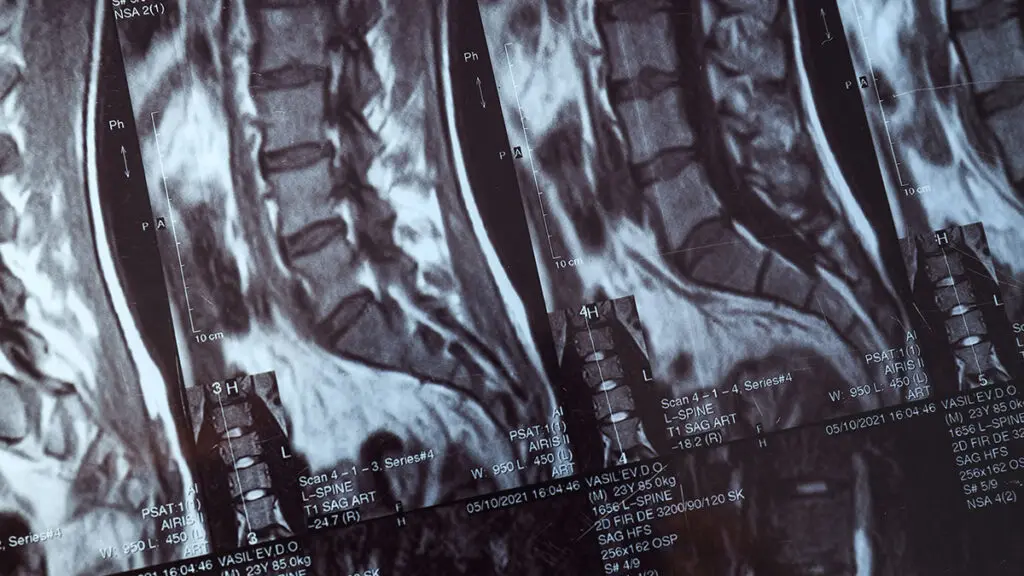

L'indicazione alla fusione vertebrale viene stabilita dopo un'accurata valutazione clinica e strumentale che include RMN, TAC e, se necessario, Rx dinamici in carico. Il piano chirurgico viene discusso con il paziente in modo trasparente, illustrando i benefici attesi, i rischi e le alternative terapeutiche disponibili.